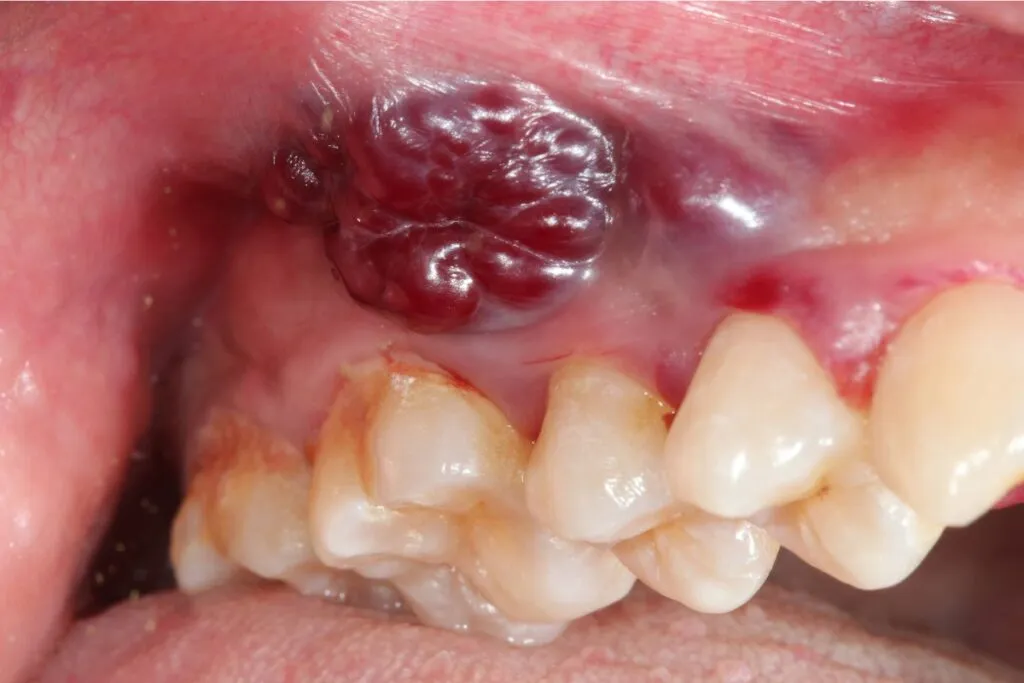

Guzek, zgrubienie lub narośl na dziąśle: jak odróżnić błahą zmianę od potencjalnego nowotworu?

Kolejnym niepokojącym objawem jest pojawienie się na dziąśle wyczuwalnego guzka, zgrubienia lub widocznej narośli. Zmiana ta może początkowo być niewielka i niebolesna, ale z czasem może stopniowo się powiększać. W przeciwieństwie do łagodnych zmian, takich jak torbiele czy zapalenia, guzek nowotworowy często rośnie bez wyraźnego powodu i może być twardy w dotyku.